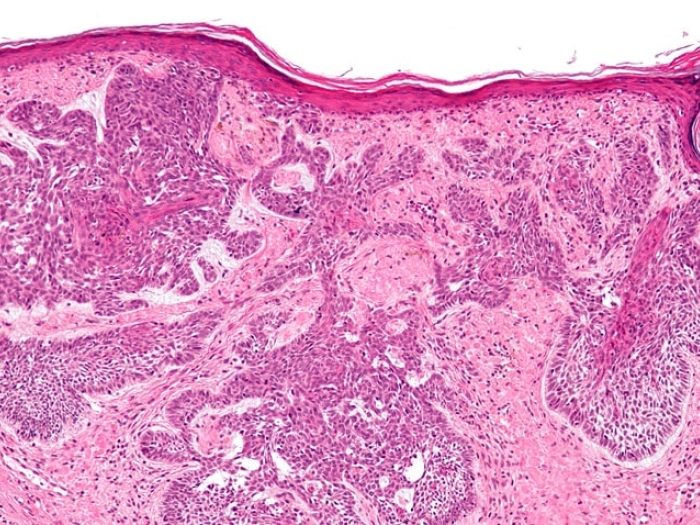

Why Basal Cell Tumors Return When Drug Treatment Stops

Researchers uncover a mechanism that explains why a Hedgehog inhibitor kills skin cancer, but not completely.